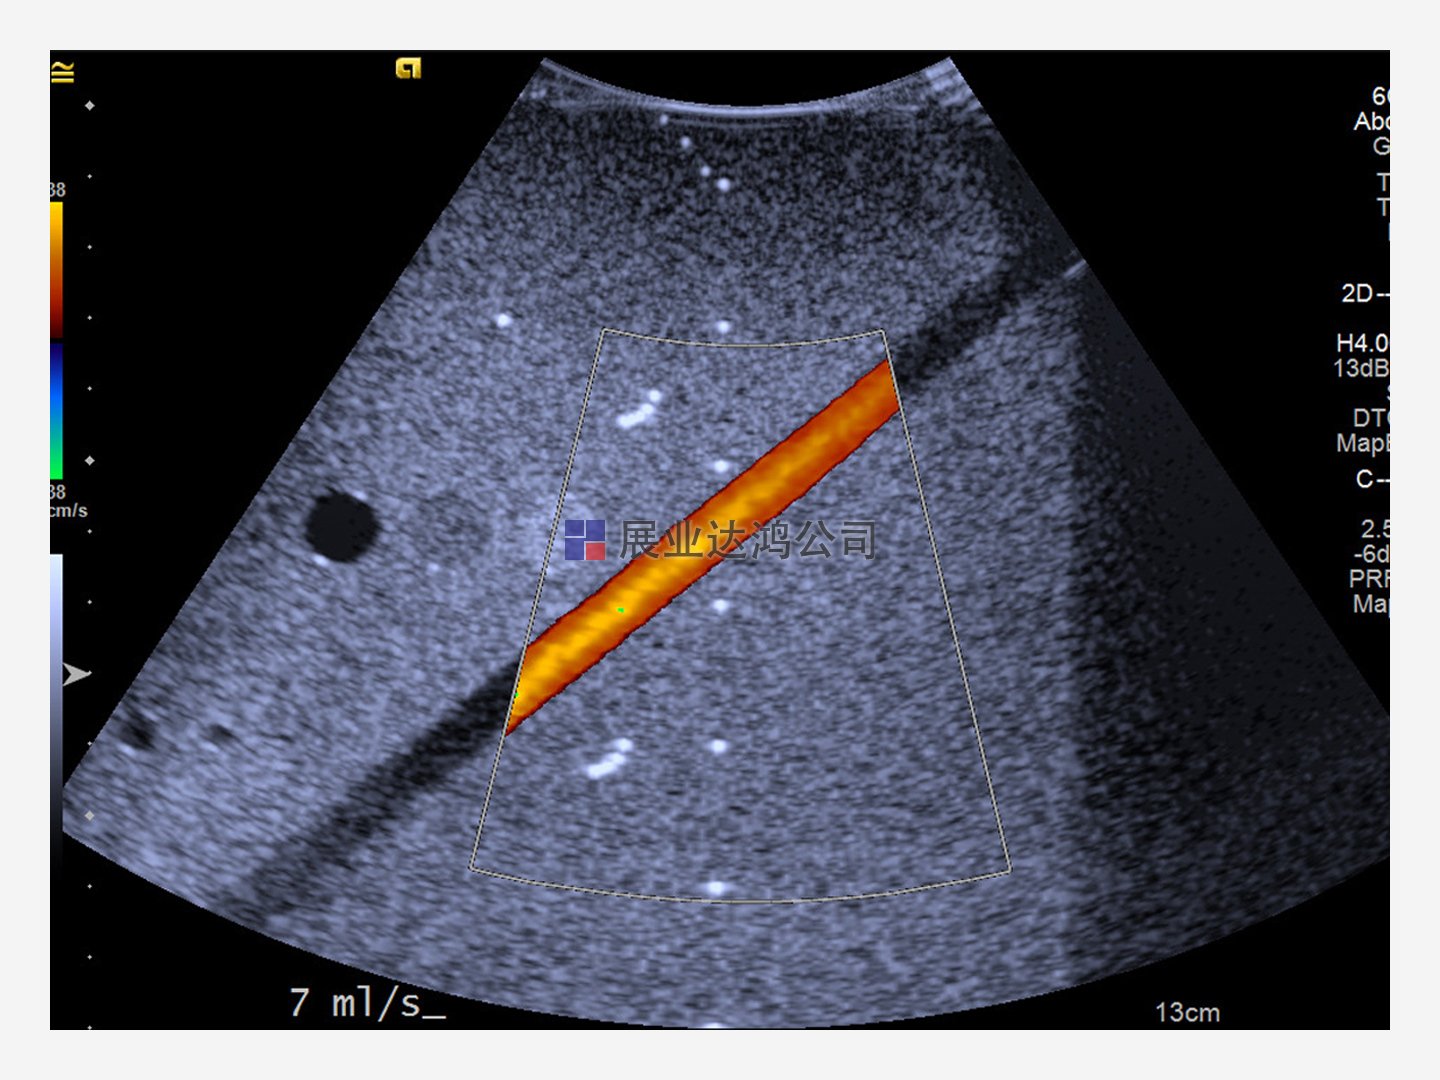

驗證超聲系統和換能器的性能。Doppler 403和 Mini-Doppler 1430流動體模使用精確的流速和專有的血液模擬流體幫助評估系統速度。

確定各種角度和光束方向的最大信號穿透、通道隔離和流速讀數精度——其能力超過 ACR、ECR、AIUM 和其他 QA 程序要求。水平段模擬頸動脈,對角段用于測量多普勒靈敏度和開發掃描技術。

提供恒定、脈動和自定義流量模式選項。體積流量設置支持可靠的系統速度測試